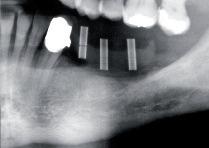

> Präoperativ wurde im Sinne eines Backward Planning erst die spätere Implantatposition und in Kenntnis dieser, die Ausdehnung des Titangitters festgelegt

> Hierbei wurde festgestellt, dass sich zum einen das Foramen mentale direkt im Augmentations und Implantationsbereich befindet und zum anderen der Verlauf des Nervus alveolaris

inferior, trotz Augmentation, nur relativ kurze Implantate zulassen wird

> Bei der digitalen Planung des Gitters wurde dieser Aspekt besonders berücksichtigt und zudem auf die Lage des Foramen mentale speziell geachtet. Das Gitter wurde im Austritts bereich ausgespart, um eine Traumatisierung zu vermeiden.

2 | Ausgeprägte, radiologische Inhomogenität des Knochens

3 | Patientenspezifische Anforderungen (z B Foramen mentale) werden für die geplante Knochenaugmentation durch die Customized Bone Regeneration (CBR®) berücksichtigt.